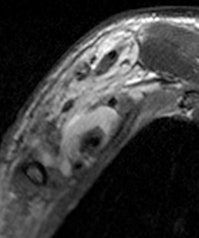

Patients ranged in age from 18 to 84 years. Their lesions detected by MRI represented a mix, including 35 root avulsions and brachial plexus cord injuries, 22 primary or secondary tumors, and four each entrapment syndromes, fibrous scars, and Parsonage-Turner syndrome.

Overall, the sensitivity for the total number of examinations analyzed on a per-patient basis was 81% and specificity was 91%. Analyzed by findings, mass lesions had the highest positive predictive value at 95%, followed by traumatic injury at 91%. The lowest was for entrapment syndromes, at 80% and 66% for post-treatment evaluation. Negative predictive values ranged from a low of 83% for traumatic injury to a high of 2% for mass lesions and post-treatment evaluations.